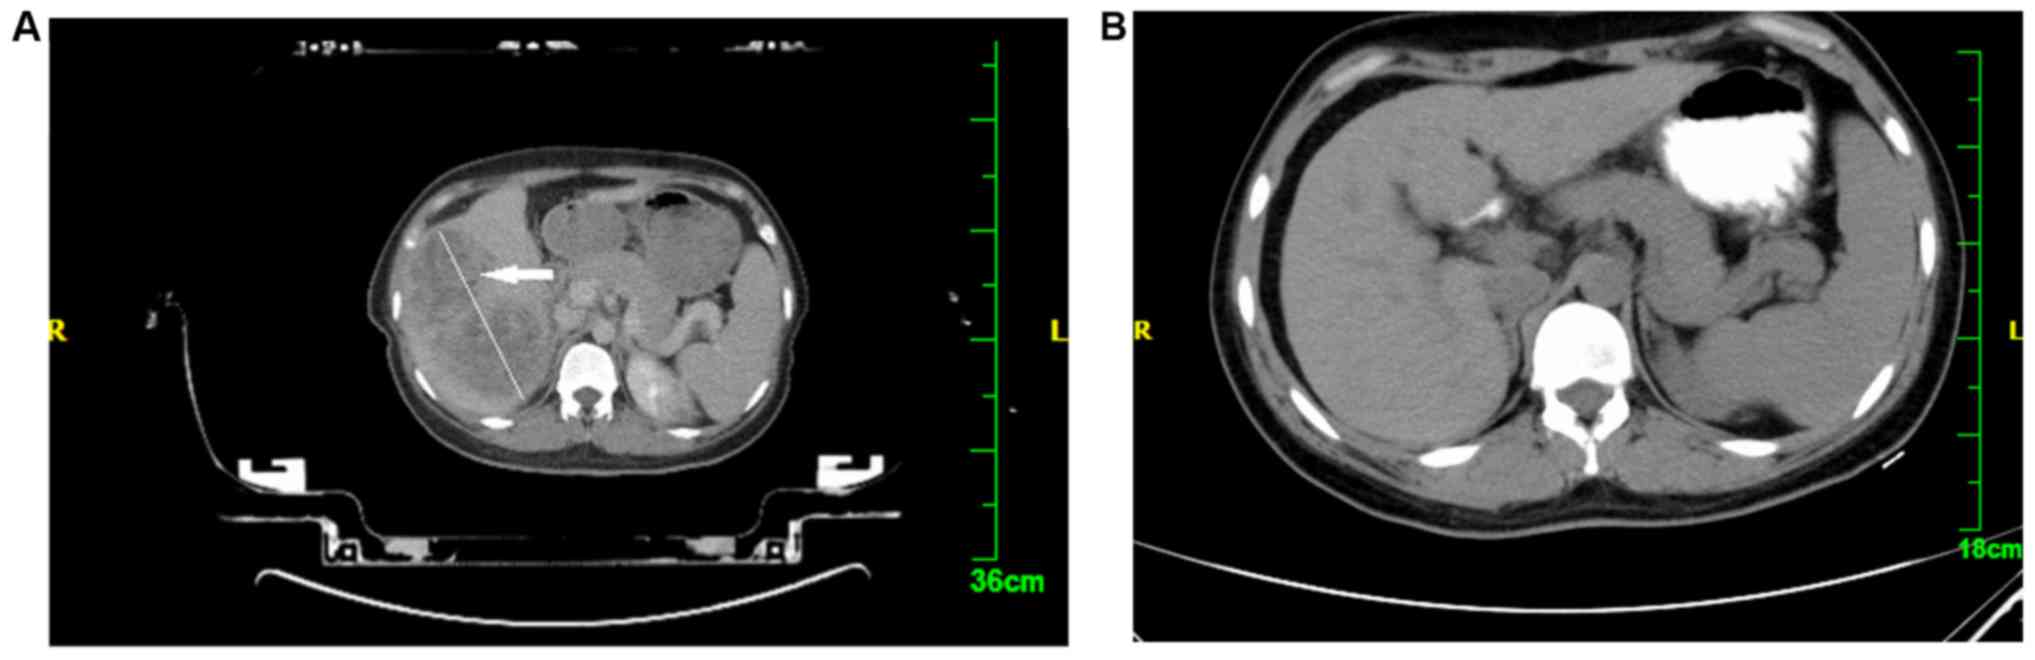

Figure 1.

Computed tomography images of a 28-year-old woman with hepatocellular carcinoma showing (A) a giant tumor (10×6 cm) in the liver (arrow) prior to radiotherapy and (B) disappearance of the tumor body, with no tumor metastasis ορ residual tumor after radiation treatment.

RT was performed using the ‘super gamma-knife’ SGS-I Stereotactic Gamma-Ray system (Huiheng Medical Inc., Shenzhen, China), which focused on whole-body radiation, and the UNICORN 3D Treatment Planning System (Huiheng Medical Inc.) for the design. RT plans were reviewed using our department's treatment planning software (Huiheng Medical Inc.). Individual gross tumor volumes (GTVs) for each liver tumor and nodal lesion visualized on positron emission tomography were generated on planning CTs. Both simulation and treatment-planning CTs were performed during breath holding. The patients were instructed to breathe quietly, as RT was repeatedly delivered during breath holding at end-expiration for 10–15 sec at a time. Using these data, the whole liver, main tumor, PVTT, and other hepatic tumors were contoured for each patient with reference to the MRI or diagnostic enhanced CT images taken within a week prior to treatment planning (Fig. 1A). Outlining of the target area-GTV was performed by a medical physicist and the planning target volume (PTV) was extended 0.5 cm outside the GTV. The organs at risk included the normal liver, duodenal pancreas, kidney and spinal cord. It was ensured that the 50% isodose curve covered the PTV and that the radiation delivered to normal tissue did not exceed the tolerance dose (Fig. 2). A dose-volume histogram (DVH) was drawn to evaluate the square and optimize the radiation scheme. The RT prescription dose was as follows: 4–6 Gy/fx, for a total of 9–12 times, 2–5 times/week, up to a total dose of 50–60 Gy. Organs of interest were avoided and the treatment plan optimization index was determined with DVH; 40 or 50% DVH surrounded the PTV (Fig. 3). The dose administered to adjacent target organs did not exceed 25 Gy (tolerance dose). During treatment, the patients were administered static drops of liquorice anhydride, while the use of chemicals was avoided.

Historically, the liver has been considered to be a relatively radiosensitive organ and it may be difficult to achieve the radiation doses required to eradicate gross tumors without causing RILD, which generally develops ~4–8 weeks following RT (9). The higher incidence of RILD in this study may be associated with the sizeable tumor and the single integral high dose and high total dose of RT. The curative effect of massive liver cancer was significant. As seen in Fig. 1, showing a pre- and post-treatment CT, the liver displayed a sizeable shadow prior to treatment, whereas the shadow completely disappeared following RT. The reason for this significant shrinking or disappearance of the tumor may be associated with high division of a single dose and the total dose.